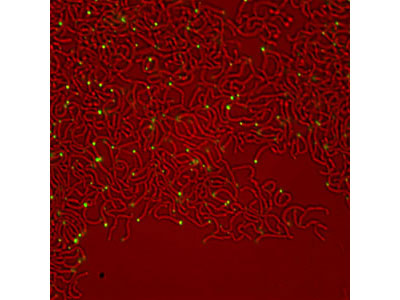

Throughout history, tuberculosis (TB) has taken a remarkable toll on human health. Even today, more than 50 years after the advent of antibiotic therapy, this infection kills millions every year. The resilience of this disease in the face of modern treatment is largely a result of the unusual biology of the causative agent, Mycobacterium tuberculosis. Our lab is focused on understanding the physiology of the mycobacterial cell, the interactions between host and pathogen, and how these fundamental biological processes influence pathogenesis and antibiotic efficacy.